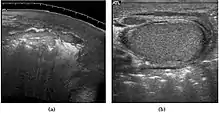

Patients with testicular lymphoma are usually old aged around 60 years of age, present with painless testicular enlargement and less commonly with other systemic symptoms such as weight loss, anorexia, fever and weakness. Bilateral testicle involvements are common and occur in 8.5% to 18% of cases. At sonography, most lymphomas are homogeneous and diffusely replace the testis [Fig. 7]. However focal hypoechoic lesions can occur, hemorrhage and necrosis are rare. At times, the sonographic appearance of lymphoma is indistinguishable from that of the germ cell tumors [Fig. 8], then the patient's age at presentation, symptoms, and medical history, as well as multiplicity and bilaterality of the lesions, are all important factors in making the appropriate diagnosis.

Primary leukemia of the testis is rare. However, due to the presence of blood-testis barrier, chemotherapeutic agents are unable to reach the testis, hence in boys with acute lymphoblastic leukemia, testicular involvement is reported in 5% to 10% of patients, with the majority found during clinical remission. The sonographic appearance of leukemia of the testis can be quite varied, as the tumors may be unilateral or bilateral, diffuse or focal, hypoechoic or hyperechoic. These findings are usually indistinguishable from that of the lymphoma [Fig. 9].

Fig. 9. Leukemia. Diffuse hypoechoic infiltrative lesions are seen involving the whole testis, indistinguishable from that of the lymphoma.